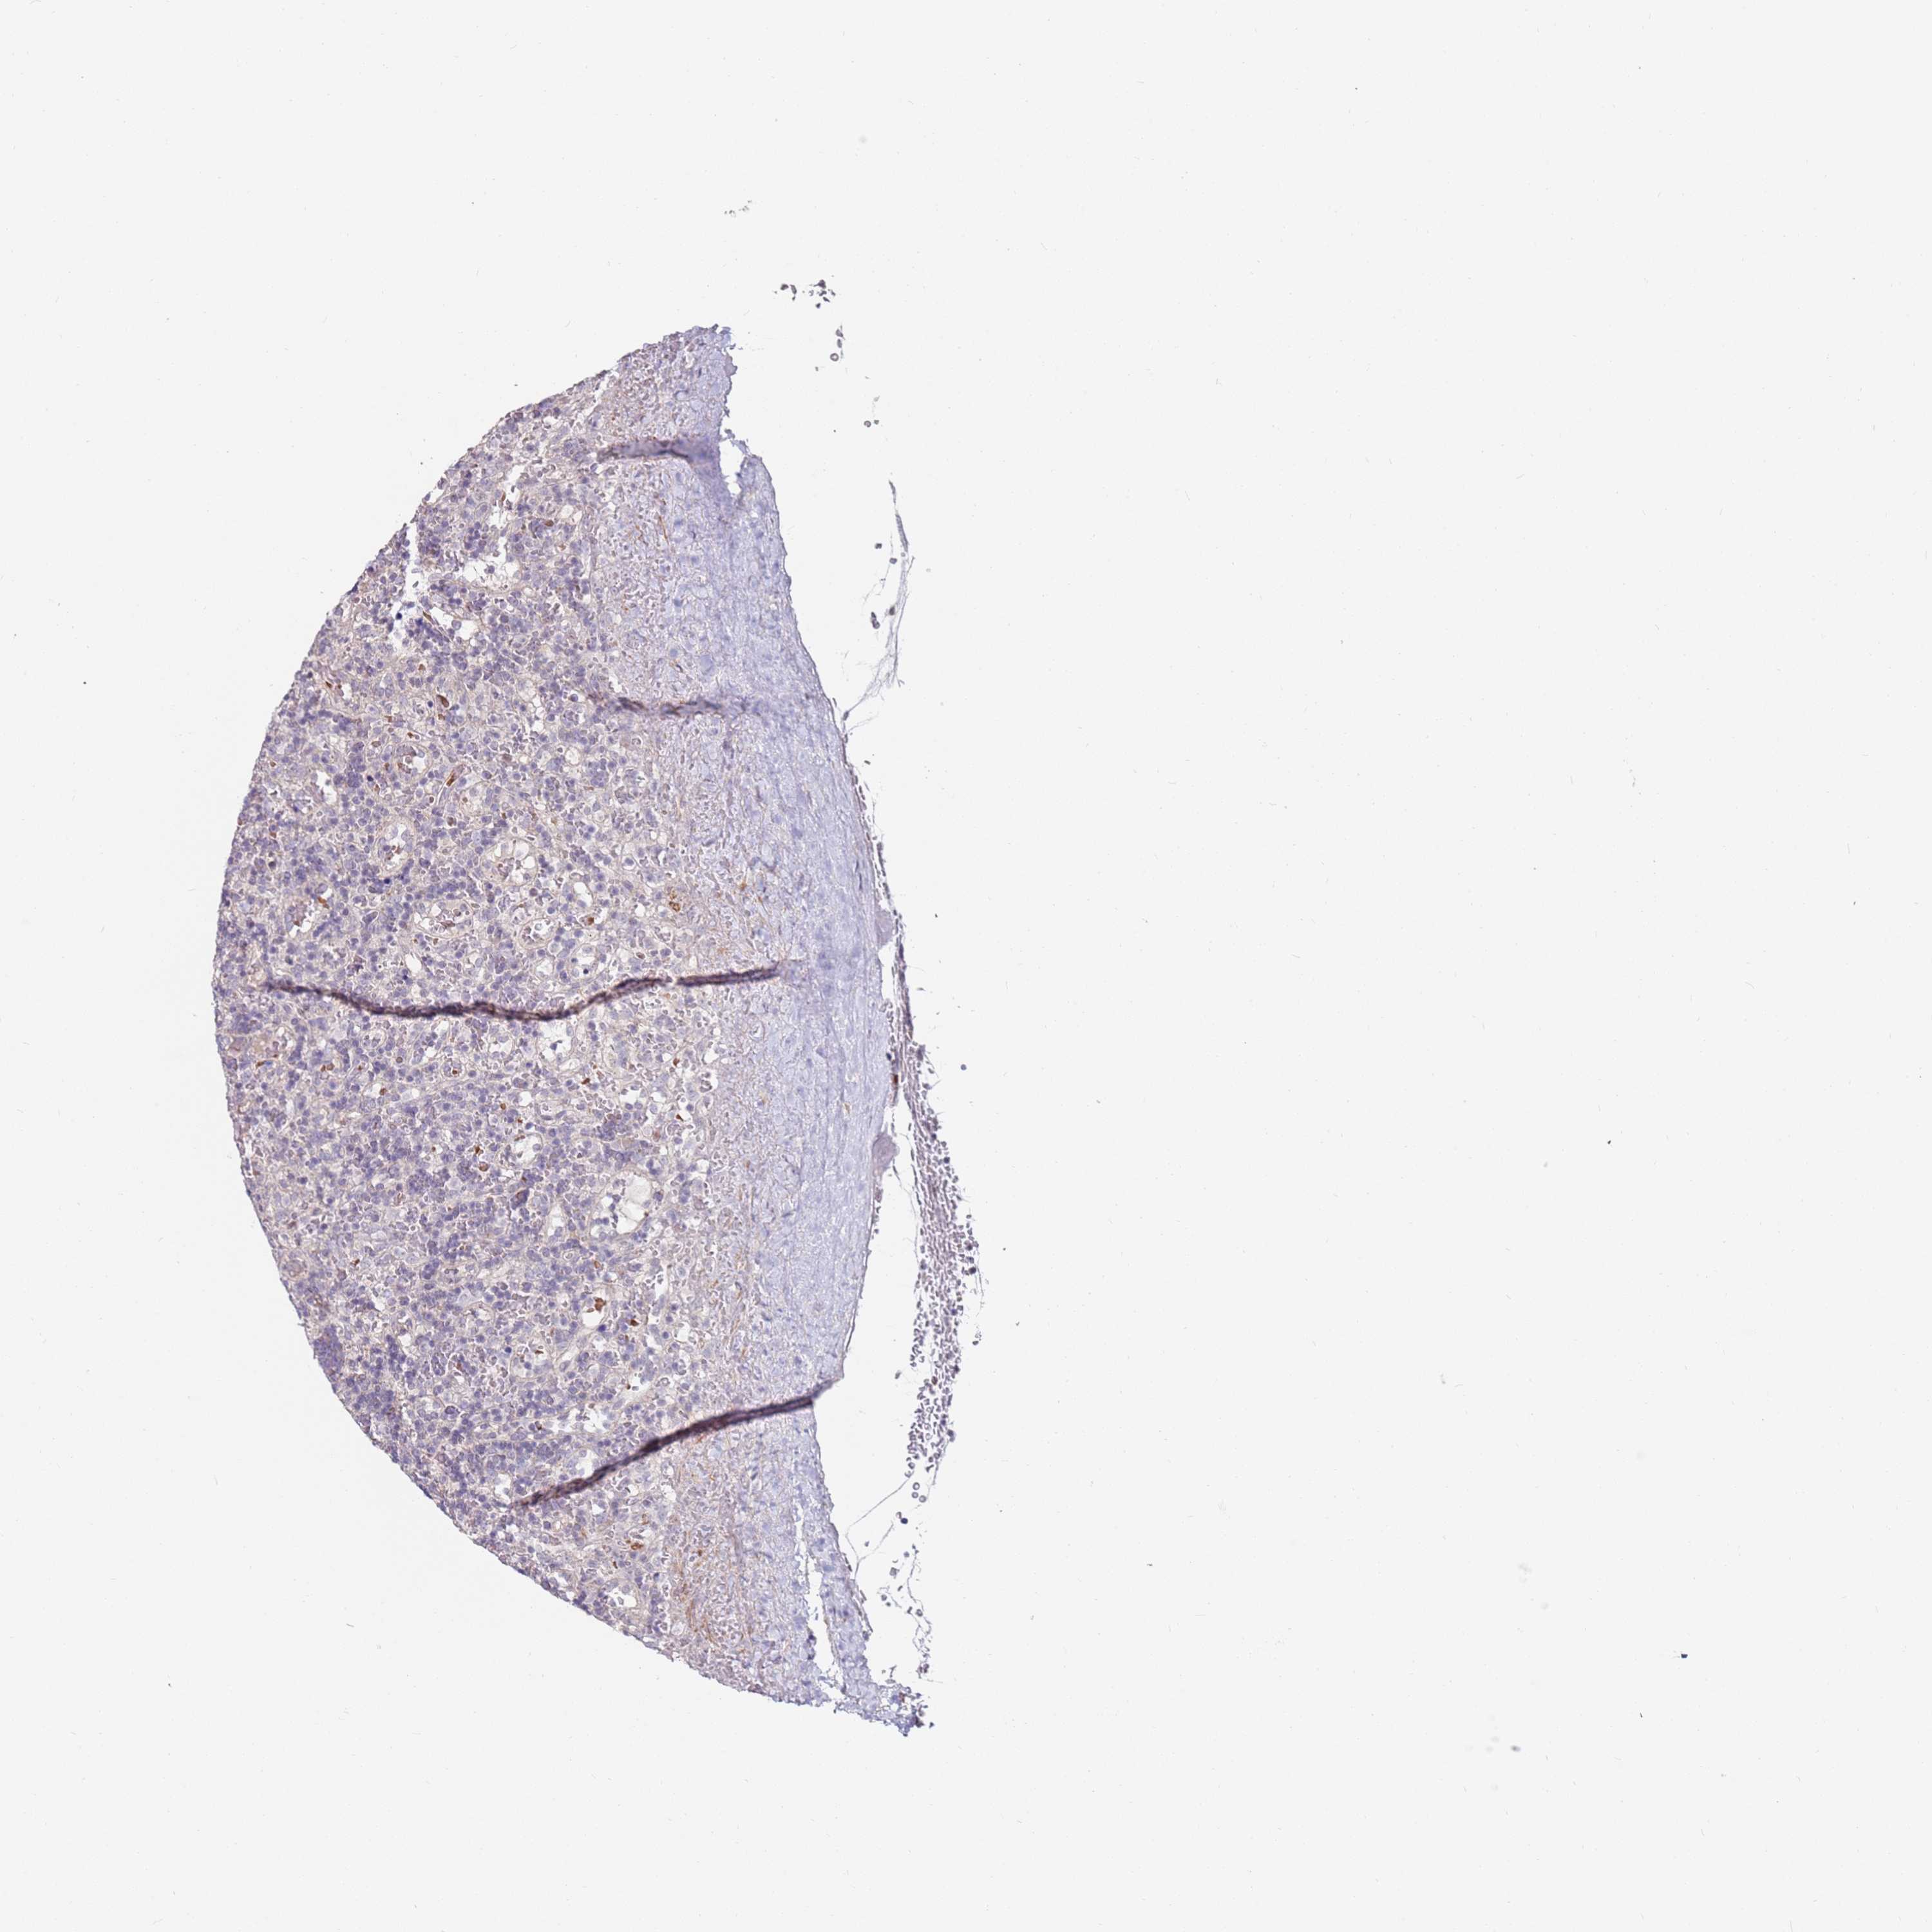

CANCER LYMPHOMA Show tissue menu

LYMPHOMA - Protein expressioni

A mouse-over function shows sample information and annotation data. Click on an image to view it in a full screen mode. Samples can be filtered based on level of antibody staining by selecting one or several of the following categories: high, medium, low and not detected. The assay and annotation is described here.

Each image is clickable and will lead to virtual microscopy that enables deeper exploration of all samples and also displays staining intensity scores, fraction scores and subcellular localization as well as patient and tissue information for each sample.

Antibody HPA039987

Antibody HPA042645

Staining

High

Medium

Low

Not detected

Intensity

Strong

Moderate

Weak

Negative

Quantity

>75%

75%-25%

<25%

None

Location

Nuclear

Cytoplasmic/membranous

Cytoplasmic/membranous,nuclear

Hodgkin's disease, NOS

Malignant lymphoma, non-Hodgkin's type, High grade

Malignant lymphoma, non-Hodgkin's type, Low grade